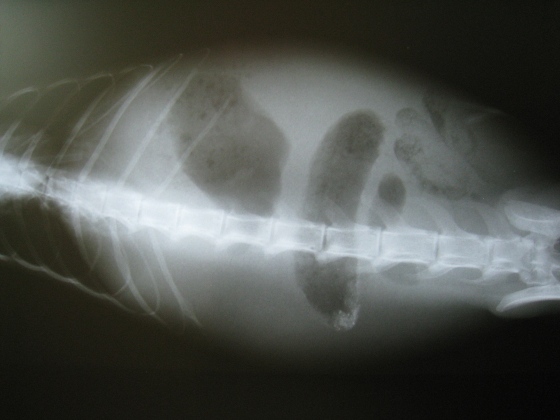

主題: 與生命在拔河的小橘貓 申請者姓名: Rita 花色: 申請日期: 2012-05-12 15:21:45 申請者部落格: 申請者臉書網址: 所在縣市/合作醫院: 新北市/銘德動物醫院 治療費用: 6670元 需求人數: 9人 已結案 (2013-02-23 14:57:28) 報名人員: 張角倫(已付款)、Hikaru(已付款)、yymeow(已付款)、Hsin Yen Cheng、王興賢(已付款)、sally(已付款)、sally(已付款)、sally(已付款)、Jane Shih(已付款)、ELaine Lee(已付款)、 候補人員: Poe Phu、小舟、 動物病情說明: 這隻小橘貓是在新莊幸福路路邊的店家門口發現的!

帶至醫院檢查後,發現有腹水,發燒,皮膚為疥癬蟲感染,嚴重貧血

檢查完初步懷疑為貓的腹膜炎感染與發病,

出現拉肚子的現象,與尿液顏色過黃,主要是因為紅血球大量被破壞的關係!